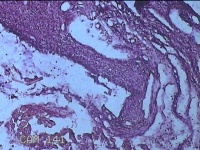

下唇包块

性别

女

年龄

38岁

临床诊断

唇粘液囊肿

一般病史

下唇包块1月。

标本名称

大体所见

灰白暗红色带皮肤样包块1.3x1x0.8cm一个,表面光滑,切开包块呈囊性,囊内充满大量粘液样物,囊壁厚0.1cm。

混合瘤